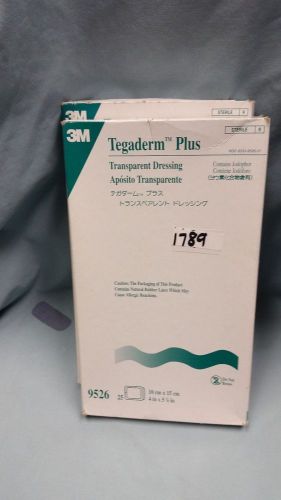

3M Tegaderm Plus Transparent Dressing 4" x 5 7/8" (9526)